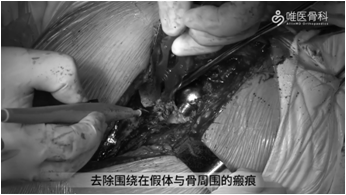

切除瘢痕组织:削薄并切除假体周围多余的瘢痕组织,常规行髋关节后脱位,并给予剥离股方肌与股外侧肌,去除围绕在假体与骨周围的瘢痕。

取出股骨假体:用骨刀去除假体近端周围的覆盖骨,使假体颈领充分显露,再用薄骨刀将假体与骨水泥界面进行分离。然后采用股骨假体专用工具取出假体,本病例采用音叉很容易就将假体取出。